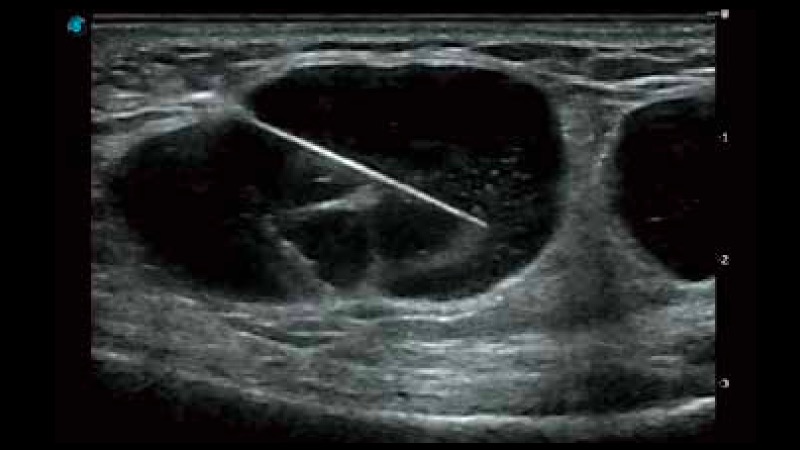

開立醫(yī)療通過不斷的技術(shù)創(chuàng)新,為大眾的生命健康提供持續(xù)關(guān)愛。P12 Plus采用全新一代超聲成像平臺,新平臺旨在將真實(shí)還原組織解剖結(jié)構(gòu)作為首要目標(biāo)。平臺采用全新集成化硬件模塊,搭載新一代芯片,系統(tǒng)性能得到大幅提升,為您的診斷提供了豐富的臨床信息。優(yōu)異的圖像表現(xiàn),豐富的探頭配置,全面的應(yīng)用功能,為您日常診斷提供了可靠的助手。